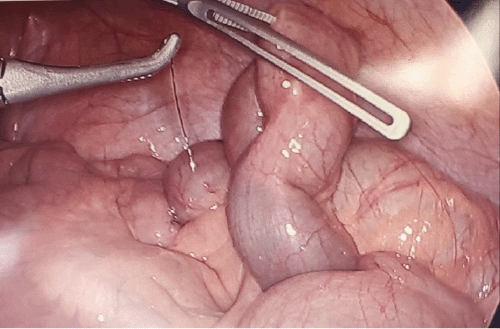

The patient was admitted to the hospital for observation; however, she did not improve with conservative therapy over 48 hours. Since the foreign body was located in the distal-terminal ileum, an attempt was made at endoscopic removal. At colonoscopy, the terminal ileum was successfully intubated; however, the foreign body could not be visualized. The next day, the patient continued complaining of right lower quadrant pain, and repeat CT imaging confirmed no progression of the foreign body within the gastrointestinal tract. At this point, the decision was made to proceed with diagnostic laparoscopy. The peritoneal cavity was entered using a 5 mm optical trocar in the left upper quadrant. The ligament of Treitz was identified, and the small bowel was run distally. At the terminal ileum, a filamentous metallic foreign body was identified protruding from the bowel wall approximately 20 cm from the ileocecal valve. The object was removed laparoscopically, and the site of perforation was repaired with imbricating sutures of 3-0 Vicryl in a Lembert fashion.

Figure 2. Two Views of Filamentous Metallic Foreign Body Perforating Terminal Ileal Bowel Wall (arrow). Published with Permission

Figure 3. Successful Removal of Metallic Foreign Body Using Laparoscopic Maryland Dissector. Published with Permission